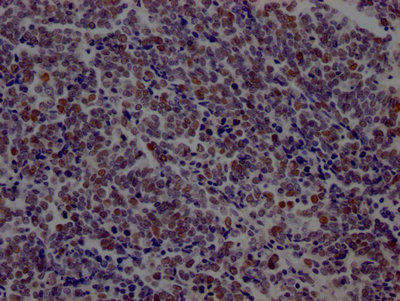

IHC image of CSB-RA877322A0HU diluted at 1:100 and staining in paraffin-embedded human lung cancer performed on a Leica BondTM system. After dewaxing and hydration, antigen retrieval was mediated by high pressure in a citrate buffer (pH 6.0). Section was blocked with 10% normal goat serum 30min at RT. Then primary antibody (1% BSA) was incubated at 4℃ overnight. The primary is detected by a Goat anti-rabbit IgG polymer labeled by HRP and visualized using 0.05% DAB.

IHC image of CSB-RA877322A0HU diluted at 1:100 and staining in paraffin-embedded human placenta tissue performed on a Leica BondTM system. After dewaxing and hydration, antigen retrieval was mediated by high pressure in a citrate buffer (pH 6.0). Section was blocked with 10% normal goat serum 30min at RT. Then primary antibody (1% BSA) was incubated at 4℃ overnight. The primary is detected by a Goat anti-rabbit IgG polymer labeled by HRP and visualized using 0.05% DAB.